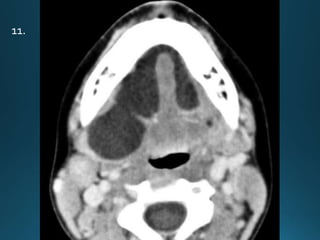

11.

External auditory canal atresia (EACA) is characterised by complete or incomplete

bony atresia of the external auditory canal (EAC)

Findings in the middle ear are variable and the inner ear and inner auditory canal are

typically normal

number of syndromes are associated with external auditory canal atresia 2.These

include:

• Crouzon syndrome

• Treacher Collins syndrome

• Goldenhar syndrome

• Pierre Robin syndrome